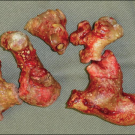

pyomyositis

02/09/2012

John W. Duff, MD

<p><img src="/sites/default/files/images/Screen%20shot%202012-02-09%20at%2011.36.03%20AM_thumb.png" width="90" height="90" style="float: left; margin:...